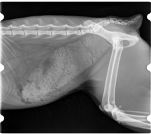

radiographie thorax chatenclouage centro médullaire fémurfracture fémur

Fracture